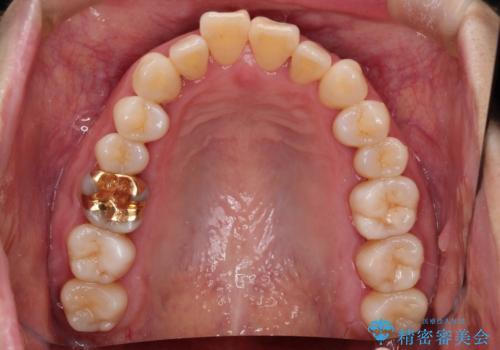

- 上下の前歯の開き(開咬)と上下前歯にガタつき(叢生)が見られます。

マウスピース矯正ではメカニクス的に開咬へのアプローチが容易です。

インビザラインの特色を生かした歯牙移動計画を作成し、非抜歯にて治療を行いました。